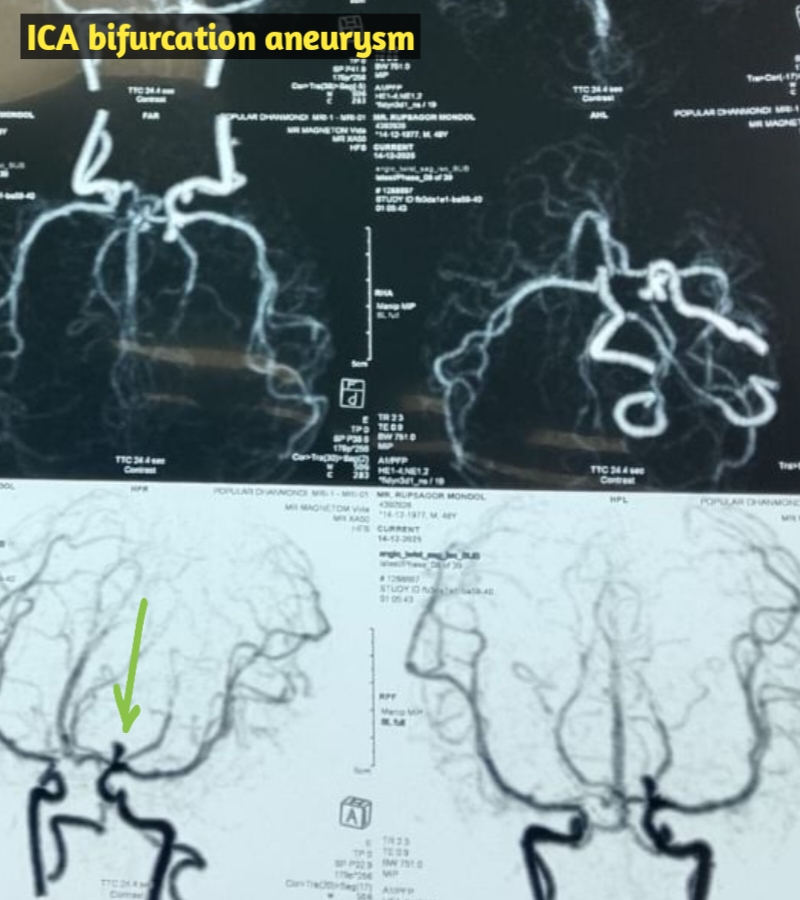

মাথা ব্যথা, ঘাড় ব্যথা, কোমর ব্যথা, পিএলআইডি সমস্যা, হেড ইনজুরি , স্পাইন ইনজুরি , স্পাইনের রড-স্ক্র ফিক্সেশন, মস্তিষ্ক - স্নায়ু - মেরুদণ্ড ব্যথা, স্পাইনাল টিউমার, ব্রেইন টিউমার, প্যারালাইসিস বা পক্ষাঘাত, স্ট্রোক, হাত - পায়ে ব্যথা, হাতে পায়ে ঝিমঝিম ভাব , শিশু নিউরোসার্জারি , ভাসকুলার নিউরোসার্জারি বিশেষজ্ঞ ও নিউরোসার্জন।